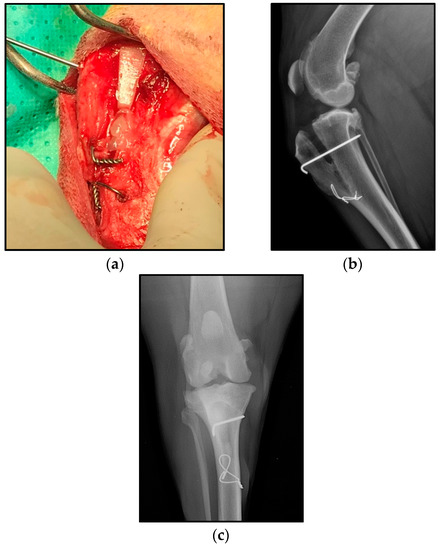

- Valiño-Cultelli, V.; Varela-López, Ó.; González-Cantalapiedra, A. Preliminary Clinical and Radiographic Evaluation of a Novel Resorbable Implant of Polylactic Acid (PLA) for Tibial Tuberosity Advancement (TTA) by Modified Maquet Technique (MMT). Animals 2021, 11, 1271. [Google Scholar] [CrossRef]

- Etchepareborde, S.; Brunel, L.; Bollen, G.; Balligand, M. Preliminary experience of a modified maquet technique for repair of cranial cruciate ligament rupture in dogs. Vet. Comp. Orthop. Traumatol. 2011, 24, 223–227. [Google Scholar] [CrossRef]

- Brunel, L.; Etchepareborde, S.; Barthélémy, N.; Farnir, F.; Balligand, M. Mechanical testing of a new osteotomy design for tibial tuberosity advancement using the modified Maquet technique. Vet. Comp. Orthop. Traumatol. 2013, 26, 47–53. [Google Scholar] [CrossRef] [PubMed] [Green Version]

- Retallack, L.M.; Daye, R.M. A modified Maquet-tibial tuberosity advancement technique for treatment of canine cranial cruciate ligament disease: Short term outcome and complications. Vet. Surg. 2018, 47, 44–51. [Google Scholar] [CrossRef] [PubMed] [Green Version]

- Ness, M.G. The Modified Maquet Procedure (MMP ) in Dogs: Technical Development and Initial Clinical Experience. J. Am. Anim. Hosp. Assoc. 2016, 52, 242–250. [Google Scholar] [CrossRef]

| Major | 2 | Tension band wiring rupture with or without tibial crest displacement (1) | 3 | Tension band wiring rupture with or without tibial crest displacement (3) |

| Implant rupture (1) | ||||